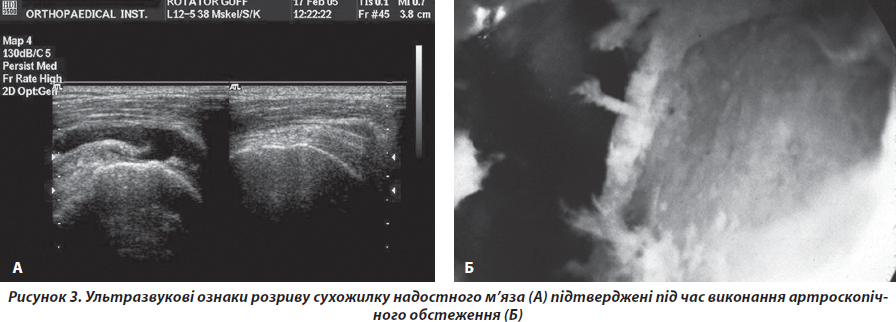

Другу групу хворих становили 128 пацієнтів (72 жінки, 56 чоловіків), середній вік 62 роки. Хворі скаржились на біль в еполетній зоні плеча під час рухів, у спокої та вночі, зниження сили або неможливість активного відведення та зовнішньої ротації плеча при збереженні або незначному обмеженні пасивних рухів. Хворі вказували на наявність травми в анамнезі. У хворих були клінічні та рентгенологічні ознаки синдрому субакроміального конфлікту. Додатково у хворих виявляли зниження сили відведення та зовнішньої ротації плеча, акустичні феномени за типом «хрусту» та «клацання» в зоні плеча. Під час виконання ультразвукового дослідження плеча виявляли ультразвукові ознаки дефекту сухожилків РМП (рис. 3).

У 62 хворих виконано магнітно-резонансну томографію плеча, де було встановлено відсутність сигналу від сухожилків РМП на фронтальних перерізах.